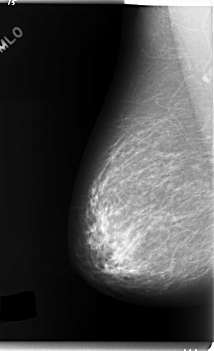

C_0124_1.LEFT_MLO

LEFT_MLO LINES 5880 PIXELS_PER_LINE 3576 BITS_PER_PIXEL 12 RESOLUTION 50 OVERLAY